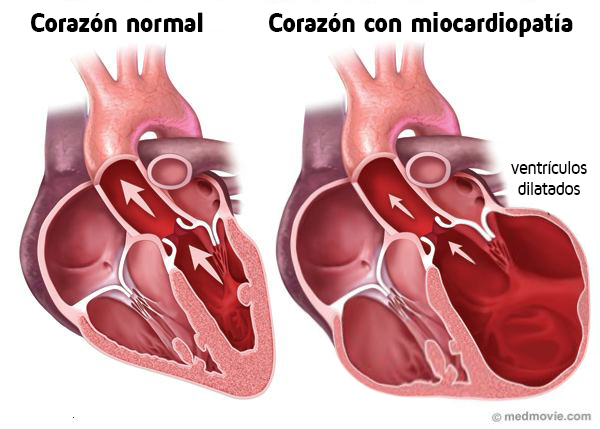

Cardiomiopatía dilatada

¿Qué es?

Patología caracterizada por una baja contractibilidad miocárdica, con o sin arritmias. Generalmente comienza en el VI, su dilatación y disfunción sistólica da lugar a las manifestaciones clínicas de IC, arritmias, y enfermedad tromboembólica. El corazón no puede bombear sangre, ya que el ventrículo se estira y se dilata, y finalmente, los órganos del cuerpo comienzan a sufrir daños por inadecuado suministro de sangre y oxígeno.

Fisiopatología

La progresiva degeneración y atrofia del los cardiomiocitos conduce a una disfunción en su capacidad de contracción, por lo que el gasto cardiaco por minuto disminuye. La actividad compensatoria simpática, hormonal y renal estabiliza mediante el incremento del volumen sanguíneo circulante, de la frecuencia cardiaca y de la presión sanguínea. El incremento de la presión al final de la diástole conduce a una dilatación de las cámaras cardiacas. Los mecanismos compensatorios llevan a una congestión venosa y en último término fallo cardiaco congestivo.

Las consecuencias hemodinámicas son que se distienden los anillos de las válvulas auriculoventriculares permitiendo el reflujo de sangre hacia las aurículas lo que aumenta la presión auricular, las aurículas se dilatan, la presión de las venas aumenta por detrás del corazón lo que termina produciendo una ICC.

En etapas finales de la enfermedad el gasto cardiaco termina por disminuir pudiendo producir un shock de origen cardiogénico, hipoxia miocárdica, arritmias y muerte súbita.